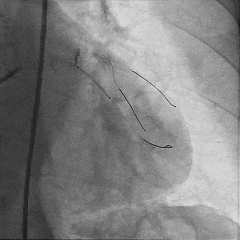

交换工作导丝至LAD远端

预扩球囊依次扩张LAD近中段病变处,造影可见远端血管显影,导丝位于真腔。

于LAD近中段植入Tivoli 2.75*33mm支架一枚,高压球囊后扩张后,血流TIMI3级